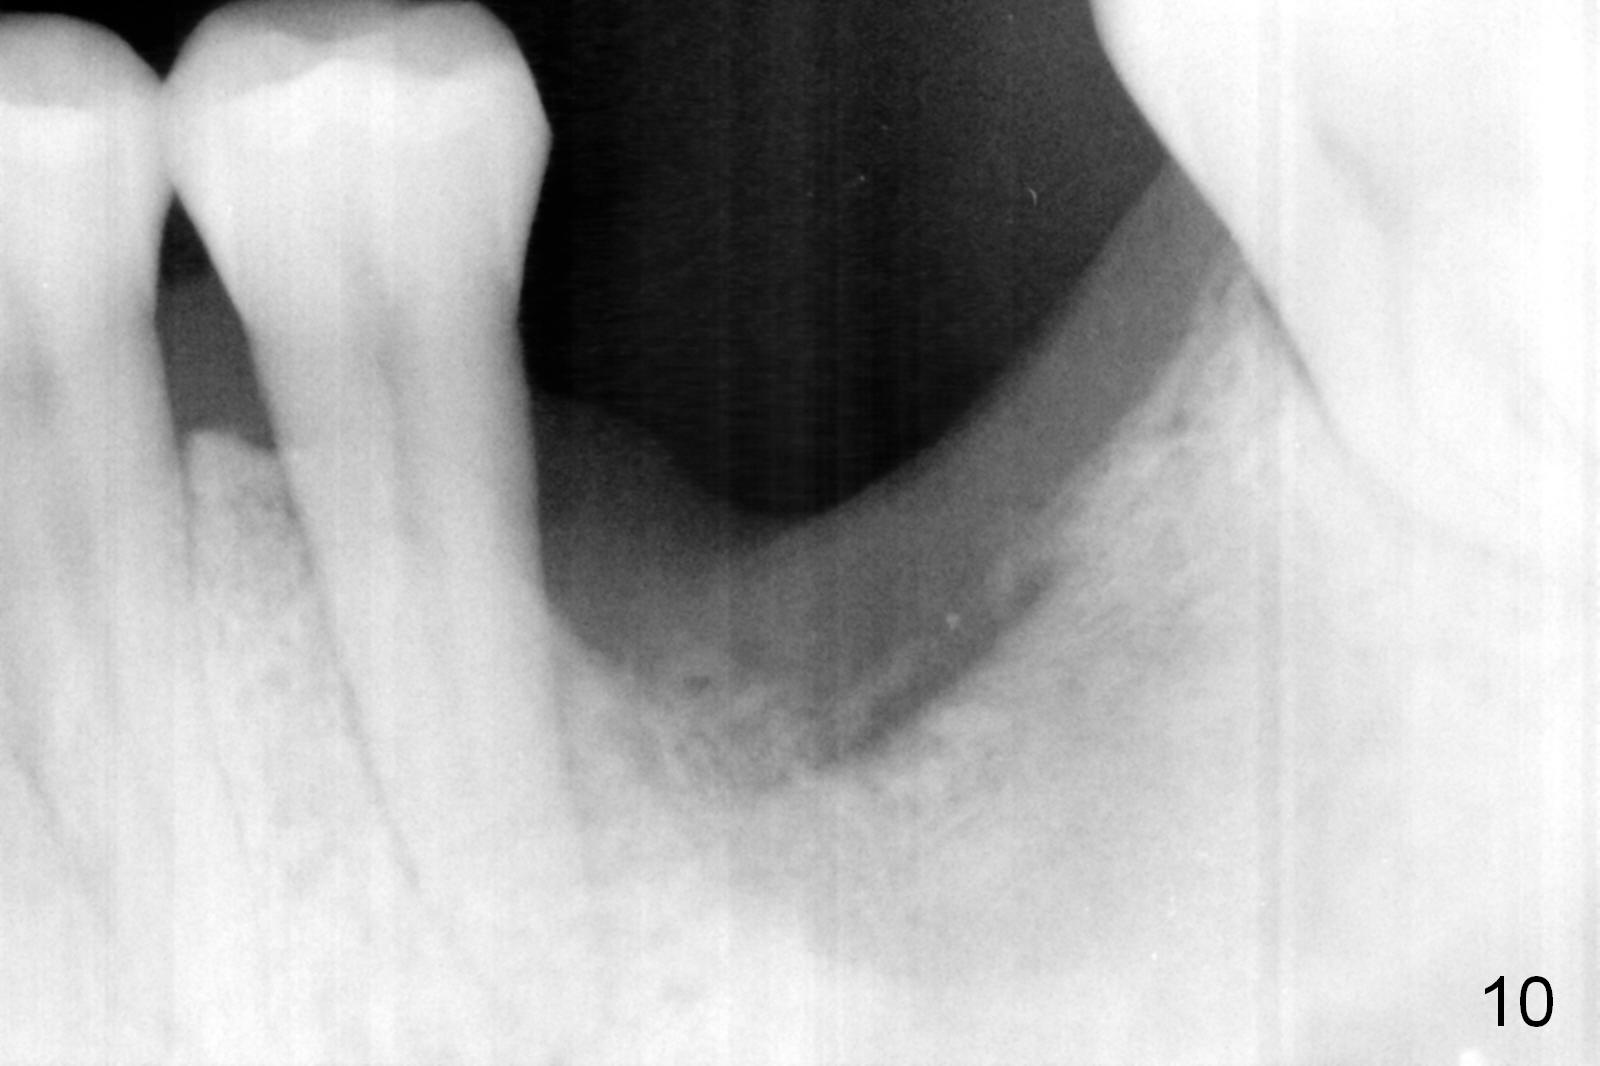

There is bone growth in the mesial socket 5 months post graft (Fig.10).  Use Magic Split to get access and test bone density (which must be low or medium in the upper portion).  Use drills beyond the socket if necessary.  Crown/implant ratio is unfavorable (Fig.11); so progressive loading is essential.